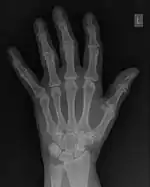

FFTs can also be calculated in two-dimensions to give results such as those in Figure 1.27. Since Fourier analysis generates results in terms of both positive and negative spatial frequencies, these can be plotted in the form of a 2D image so that the maximum frequency lies at the origin and those for the horizontal and vertical directions are shown increasing towards that origin. The modulation at different spatial frequencies is represented using a grey-scale. Low frequency bands can be seen along the horizontal axis in the figure, for example, representing the horizontal periodicity of image data from the fingers, while finer bands along the y-dimension are indicative of a periodicity of image data from the various metacarpophalangeal joints. Higher frequency features can also be seen running diagonally in this 2D-FFT, representative of the trabecular structure of the bones, for example.

The essence of this approach is that it can be used to produce a range of image processing effects by enhancing and/or suppressing features in the 2D-FFT and then converting the result back into the spatial domain using the IFT, as illustrated in Figure 1.28. Such image manipulations are considered in more detail in a later chapter. Note that the form of image processing demonstrated in the figure is for purely illustrative purposes and bears no direct medical significance.

![]() Fig. 1.28(a): A radiograph of the wrist. | ![]() Fig. 1.28(b): The wrist radiograph processed by attenuating periodic structures of size between 1 and 10 pixels. |